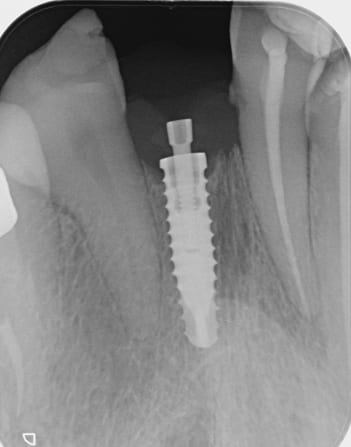

Nous avons besoin d'identifier cet implant.

Avez vous une idée ?

Rien trouvé pour l’instant